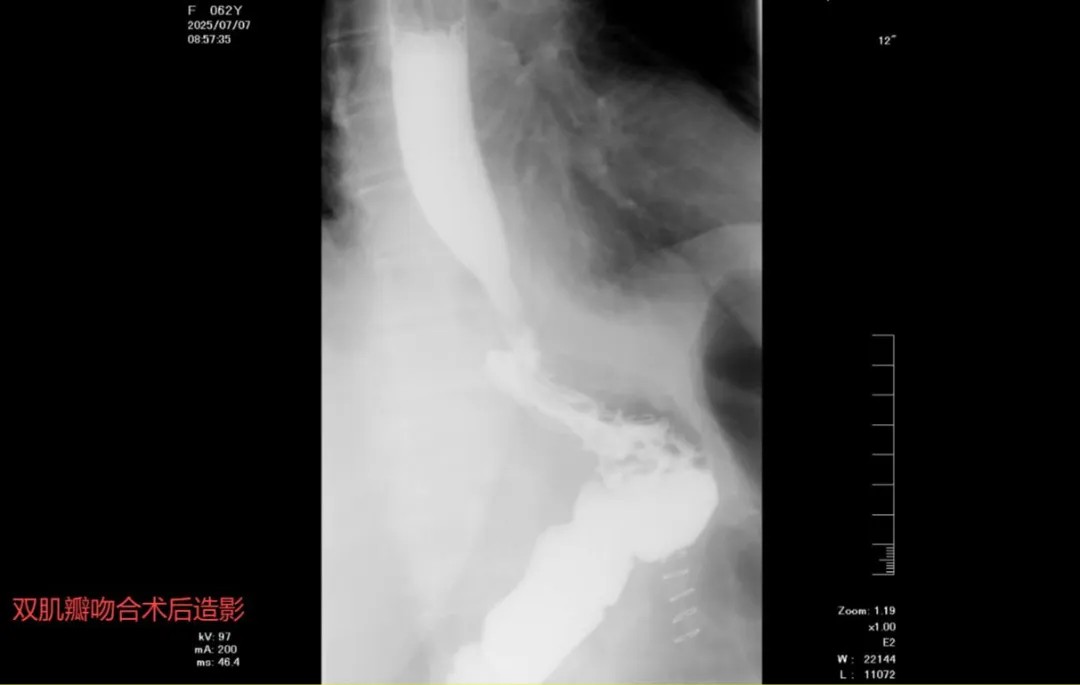

近日,山西省医院协会常务理事单位——临汾市人民医院胃肠外二科张晓峰团队完成首例完全腹腔镜近端胃切除双肌瓣吻合术(Kamikawa方法)。患者术后饮食正常,恢复良好。

传统的近端胃切除手术,由于切除了正常贲门结构,失去其抗反流作用,易出现严重的反流性食管炎,引起反酸、烧心,患者多数无法平躺休息,被迫坐位,生活质量严重下降。为了改善患者术后反酸烧心症状、提高患者生活质量,抗反流保功能成为临床关注热点,并出现多种改良术式,包括近端胃切除双通道间置空肠吻合术、近端胃切除双肌瓣吻合术(Kamikawa方法)等。双肌瓣吻合术相当于再造贲门,可减少反流性食管炎的发生,明显改善患者术后生活质量,目前已成为国内及国际上近端胃切除术后首推消化道重建方式之一。但由于该术式技术要求高,尤其腹腔镜下操作要求术者拥有精细的操作、扎实的腔镜技术,因此目前省内乃至国内可完成完全腹腔镜近端胃切除双肌瓣吻合术(Kamikawa方法)者较少。